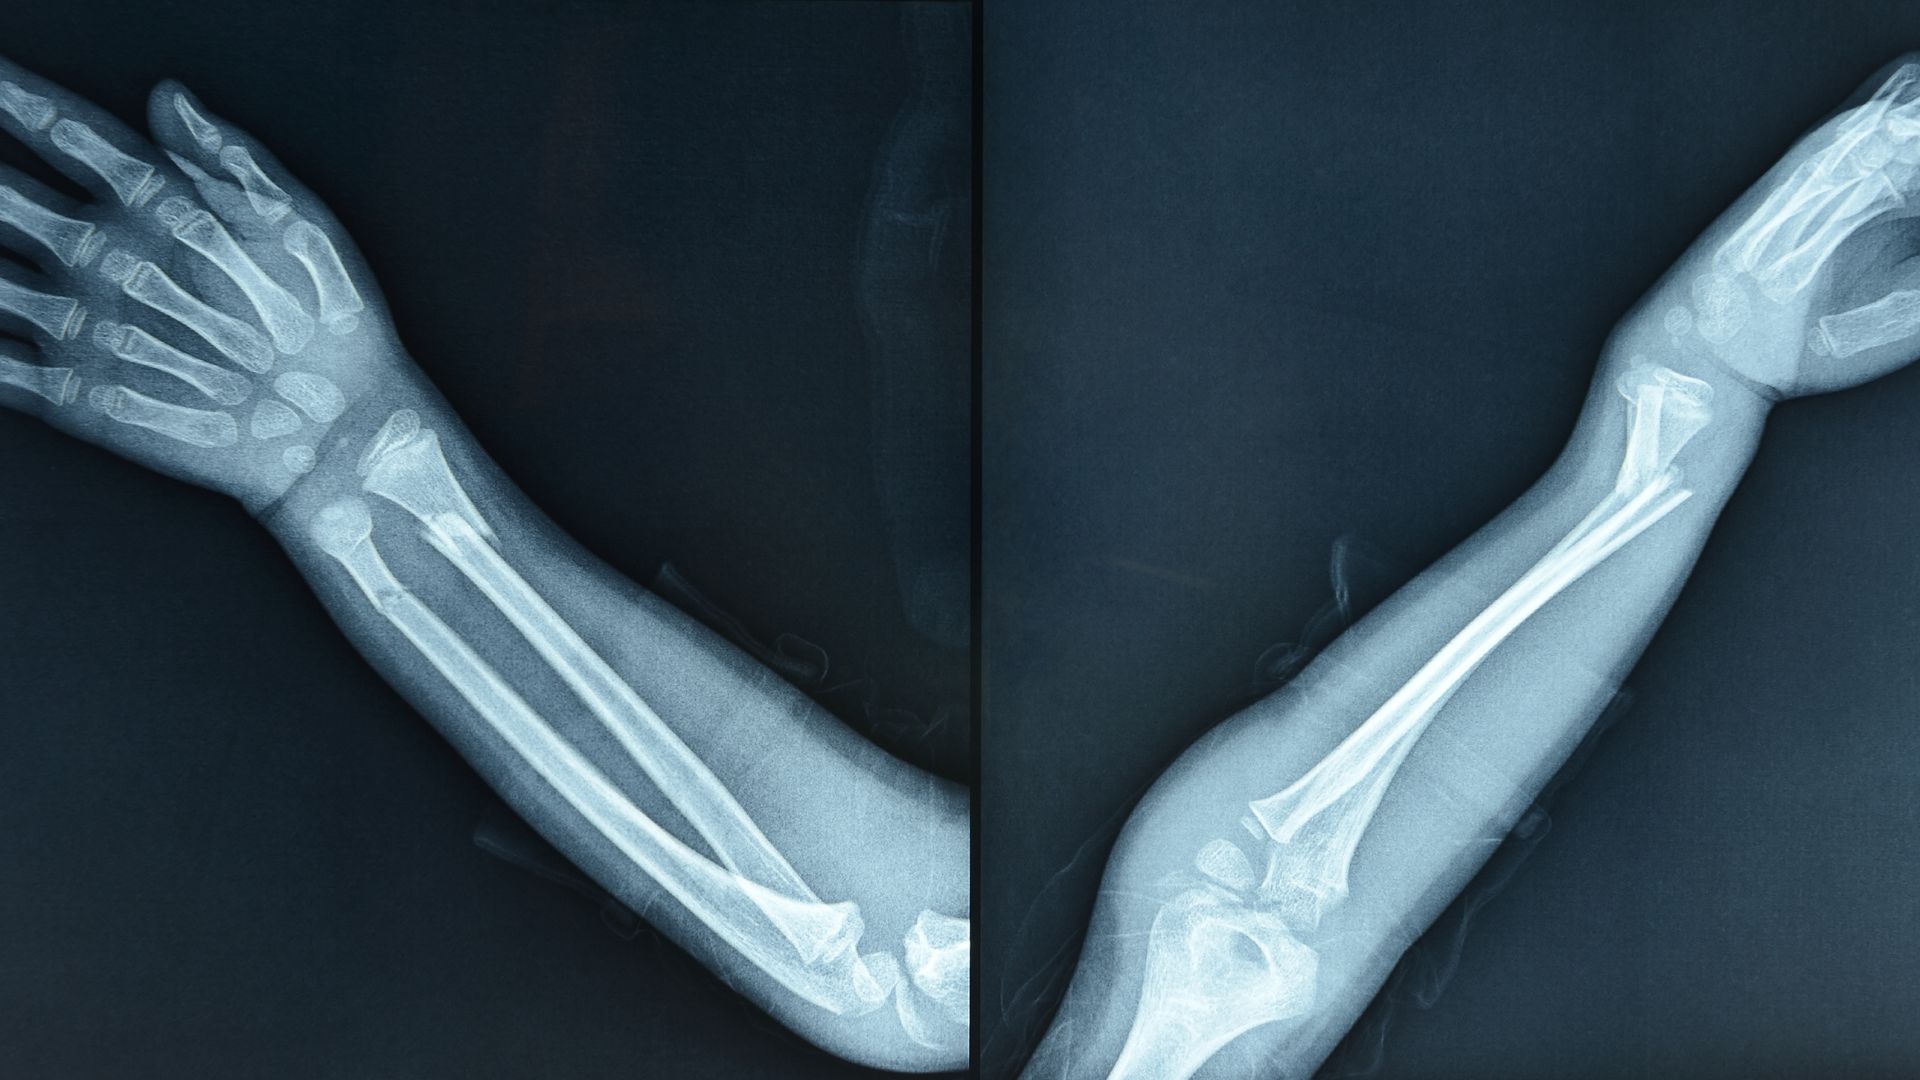

- Chụp X-quang: Là bước cận lâm sàng đầu tiên, giúp xác định vị trí gãy, mức độ di lệch và số đoạn xương bị tổn thương.